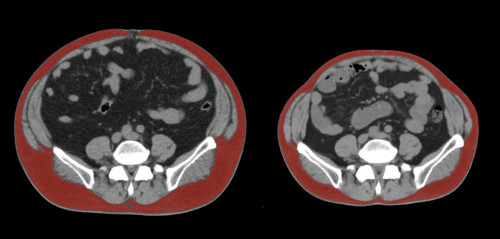

②

40代・女性(ご本人のご厚意で画像提供)

治療内容:チルゼパチド2.5mgの週1回自己注射による脂肪減少と脂肪肝改善

治療期間: 6ヶ月(26週)((用量は2.5mgから開始し最大で15mg。減量効果が得られる必要用量には個人差があります。))

費用:自由診療の場合は4400円(税込)×26(週)=114400円

想定されるリスク・副作用:下記に副作用を記載

※医療広告ガイドラインに準拠して表記

1:脂肪の減少

皮下脂肪の減少(赤色部分)